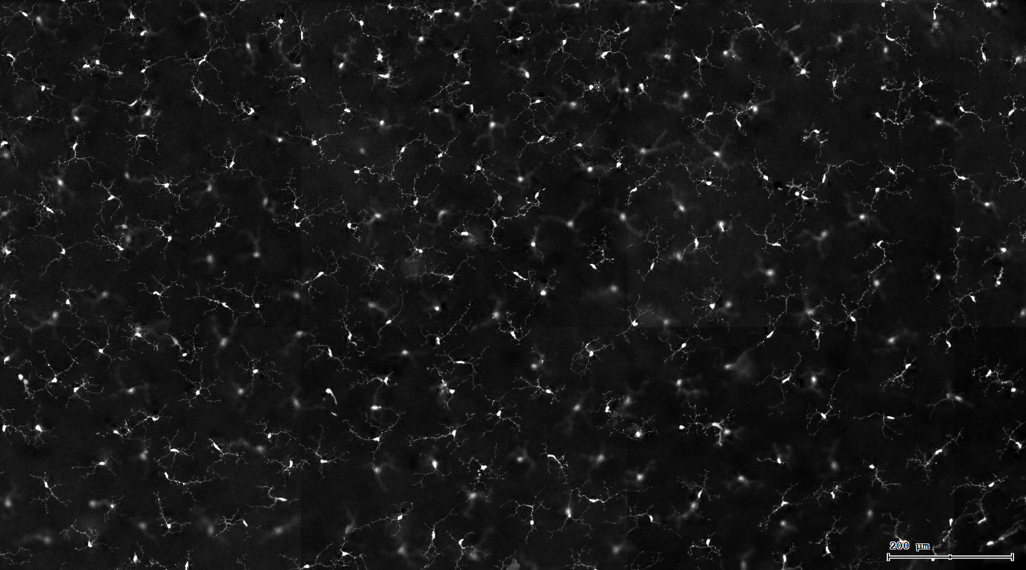

3. 根据FITC通道识别神经胞体并筛选出有效细胞胞体(细胞核识别算法)。

4. 膜识别FITC染色信号的区域确定神经纤维,并对不同长度神经纤维进行分类。

根据染色强度,染色面积,细胞形态学,利用正反向回溯功能和设门圈选Gating,排除杂质,细胞碎片,黏连细胞(绿色框线标记),获得有效的神经元胞体,(粉色框线标记),并将胞体按照面积分为两类(散点图)。

由于该视网膜样本是标记的小胶质细胞,根据面积将神经胞体分为两类(Small bodycell,Big bodycell),反向回溯Big bodycell中的细胞后,应用Input Gate功能筛选短粗的神经纤维,作为激活态的小胶质细胞。

激活态小胶质细胞识别